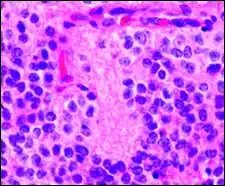

Micrograph of pineocytomatous/neurocytic pseudorosettes Micrograph of pineocytomatous/neurocytic pseudorosettes

Histologic features of these two tumors are virtually identical, including their tendency to form neuropil-rich rosettes, referred to as pineocytomatous/neurocytic rosettes in central neurocytoma. Both are quite similar to the Homer-Wright rosette, but they are generally larger and more irregular in contour. The cells of the pineocytomatous/neurocytic rosettes are also considered to be much more differentiated than the cells forming Homer-Wright rosettes in that the nuclei are slightly larger, more rounded, much less mitotically active, and paler or less hyperchromatic. In rare cases, these rosettes may aggregate in a sheet of back-to-back clusters resembling fieldstone pavement.[2]